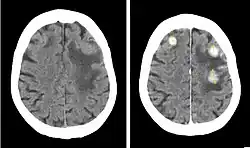

Iopentol (trade name Imagopaque) is a pharmaceutical drug that was used as a radiocontrast agent for X-ray imaging in Europe.[1]

Iopentol is an iodine-containing, water-soluble radiocontrast agent. The iodine atoms readily absorb X-rays, resulting in a higher contrast of X-ray images. It has a low osmolality, meaning that the solution has a relatively low concentration of molecules; this is usually associated with fewer adverse effects than high-osmolality contrast agents.[1][2]